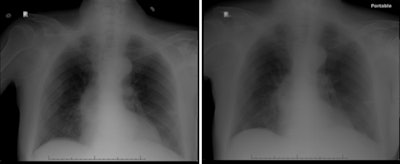

For the study, the researchers collected 100 musculoskeletal and 100 chest radiographs for which the corresponding technologist chose to retake an image citing an issue with image quality. Musculoskeletal radiographs were obtained in February 2015 from an outpatient musculoskeletal imaging center, while chest radiographs were obtained during October to December 2015 from an affiliated hospital.

Rosenkrantz, Recht, and colleagues found that out of the 95 musculoskeletal cases, 74 could have been resolved without a repeat image. And out of a total 87 chest cases, 81 could have been handled with the original image alone.

Although the repeat images demonstrated noticeable improvements in quality, the radiologist often did not agree with the reason for repeating the image and the clinical question frequently could have been answered without having to repeat the image, they noted.